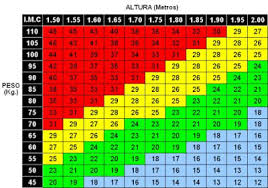

678 × 518 - gimolimpo.com

{"cb":15,"id":"jpp4X3OVBi6CfM:","isu":"gimolimpo.com","itg":0,"ity":"jpg","oh":518,"ou":"http://www.gimolimpo.com/PAGINA%2040/Castup_tv%20-%20The%20largest%20streaming%20platform%20for%20live%20streaming%20,%20live%20broadcasting%20and%20more___archivos/fondo_dieta_3.jpg","ow":678,"pt":"fondo_dieta_3.jpg","rid":"fqzWY27NIw7kDM","rmt":0,"rt":0,"ru":"http://www.gimolimpo.com/PAGINA%2040/INDICE%20MASA%20CORPORAL.htm","s":"Se

considera que una persona tiene un peso normal cuando tiene un índice

de masa corporal inferior a 25, entre 20 y 24 para las mujeres y entre

20 y 25 para

...","sc":1,"th":196,"tu":"https://encrypted-tbn0.gstatic.com/images?q\u003dtbn:ANd9GcTNxN-cKcd-O4XYTNYStZff7LMytZn8CAb7XGv9aZCsd9KEqRF4vw","tw":257}

350 × 225 - gimolimpo.com

{"id":"eD7cRRkVLMiQpM:","isu":"gimolimpo.com","itg":0,"ity":"jpg","oh":225,"ou":"http://www.gimolimpo.com/PAGINA%2029/Tabla_IMC.jpg","ow":350,"pt":"gim

olimpo","rid":"PDBNppOb_qodpM","rmt":0,"rt":0,"ru":"http://www.gimolimpo.com/PAGINA%2029/I%20M%20C.htm","s":"Hoy

habia 451 Visitantes (2439 número de aciertos) ¡Aqui en esta

página!","sc":1,"th":180,"tu":"https://encrypted-tbn0.gstatic.com/images?q\u003dtbn:ANd9GcQ4hZv433jUY5siYozITKpARz0jX6WrzceI_YJgTLwkbHfpdYGD","tw":280}